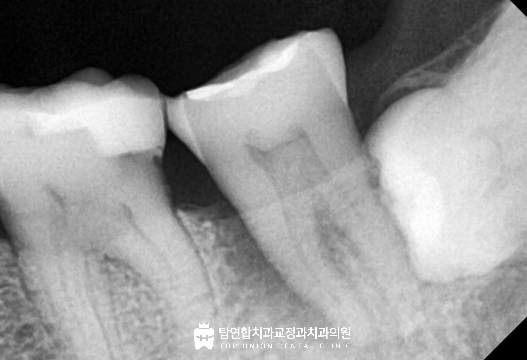

작은 x-ray 사진에서는 해당 어금니의 근심 쪽 잇몸뼈가

까맣게 흡수되고 있는 모습이 보였고

잇몸 상태와 동요도 검사 결과를 종합해 분석한 결과

통증은 빠르게 감소했으며 x-ray 상에서 보였던

근심 부분의 파괴되었던 치조골이 회복 양상을 보였습니다.